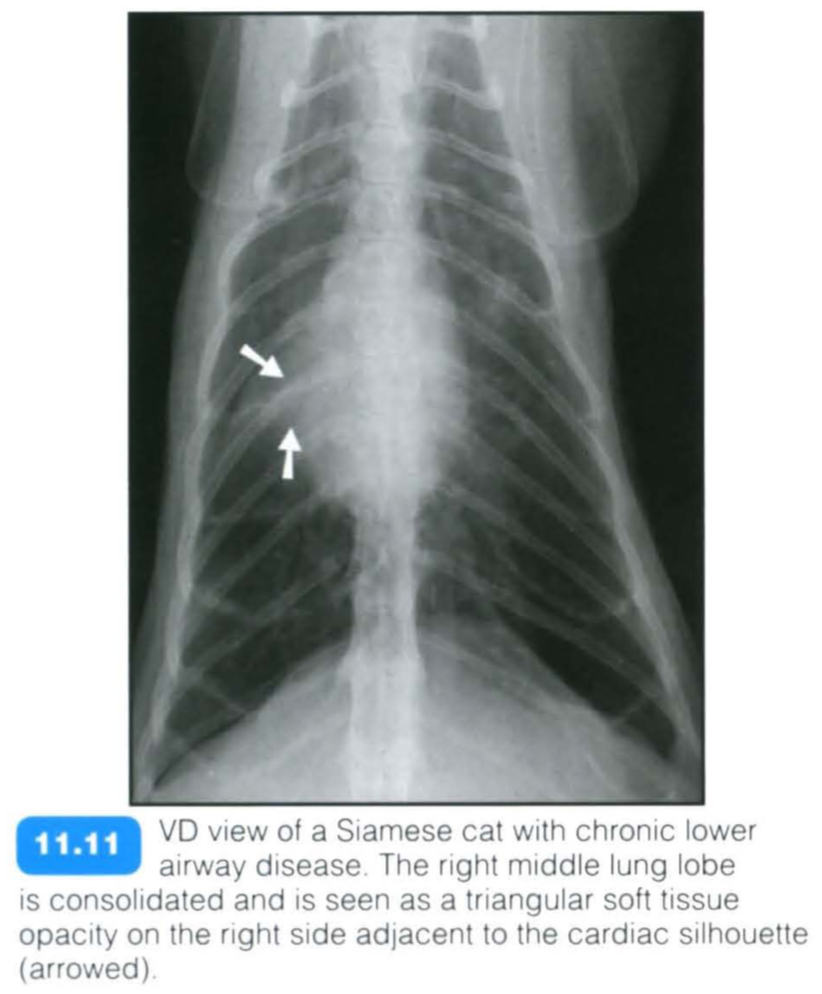

Feline chronic lower airway disease

Feline chronic lower airway disease encompasses a multitude of small airway diseases in the cat including feline asthma. Inflammation of the airways leads to a reversible obstruction to airflow (functional obstruction) and hence air trapping. The obstruction is due to a combination of bronchoconstriction, bronchial wall oedema and submucosal gland hypertrophy.

Clinical signs vary from chronic coughing and wheezing to severe respiratory distress. The condition can affect cats of any age with Siamese appearing to have an increased incidence . Hyper-responsive airways and reversible airflow obstruction lead to a reduced airway diameter and increased airway resistance. The condition can be extremely severe in presentation and care should be taken when handling dyspnoeic cats.